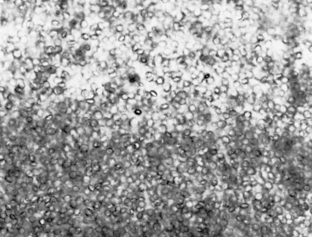

Nematodes (Roundworms): The bovine trichostrongyles are composed of several genera of nematodes within the abomasum and small and large intestine of cattle and other ruminants. Genera that produce trichostrongyle-type eggs are Bunostomum, Cooperia, Chabertia, Haemonchus, Oesophagostomum, Ostertagia, and Trichostrongylus. These seven genera (and others) produce oval, thin-shelled eggs. They contain four or more cells and are 70 to 120 μm long. Some of these ova may be identified to their respective genera; however, identification is usually difficult because mixed infections of bovine trichostrongyles are quite common.

Upon identification of the characteristic eggs, the veterinary technician should record the finding as a trichostrongyle-type egg (Fig. 6-34). They should never be recorded as individual genus names. Identification of genus and species usually can be performed only by fecal culture and larval identification.

Figure 6-34 Characteristic trichostrongyle-type ova of the bovine trichostrongyles. These oval, thin-shelled eggs contain four or more cells. They measure 70 to 120 μm long. Some of these ova can be identified by their respective genus; however, identification is usually difficult because mixed infections are common. (From Hendrix CM, Robinson E: Diagnostic parasitology for veterinary technicians, ed 3, St Louis, 2006, Mosby.)